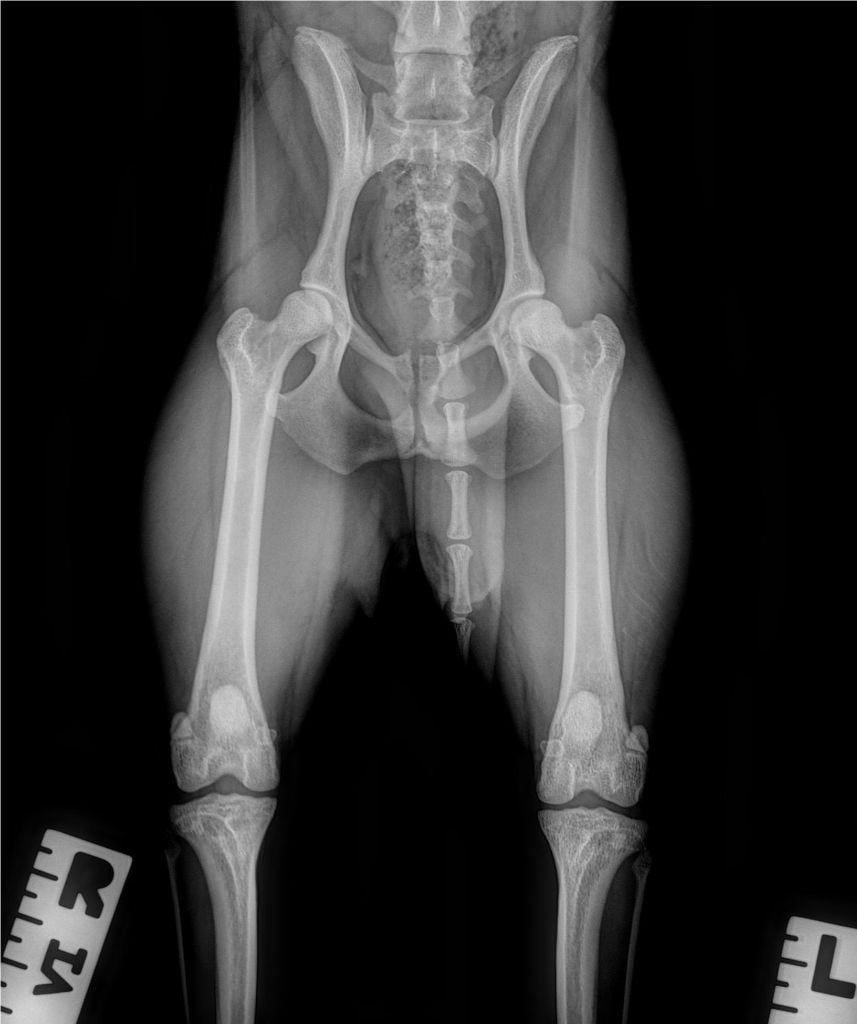

Radio de Dysplasie des Hanches de Suerte LJ Des Jardins De Margaux

Carte ADN : OK Compatibilité de Filiation : OK MHOC : RAS PATELLA (Rotules) : 0/0 Radio de dysplasie : A / B echo doppler coeur : RAS echo doppler reins : RAS |